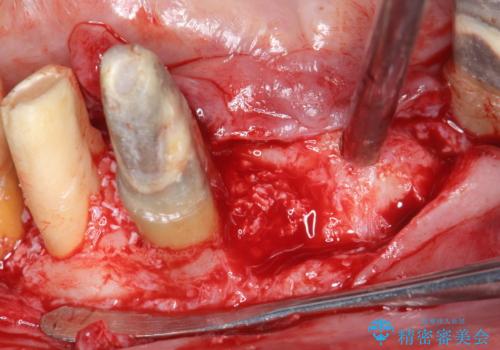

残すことのできない歯を抜去し、入れ歯になることを回避すべくブリッジ治療を行いますが支台となる歯の歯周病を改善すべく歯周病により溶けた歯槽骨の再生治療を計画します。

再生治療により良好な歯槽骨の再生が得られ、入れ歯ではなく取り外しの必要のないブリッジによる機能回復を行うことができました。